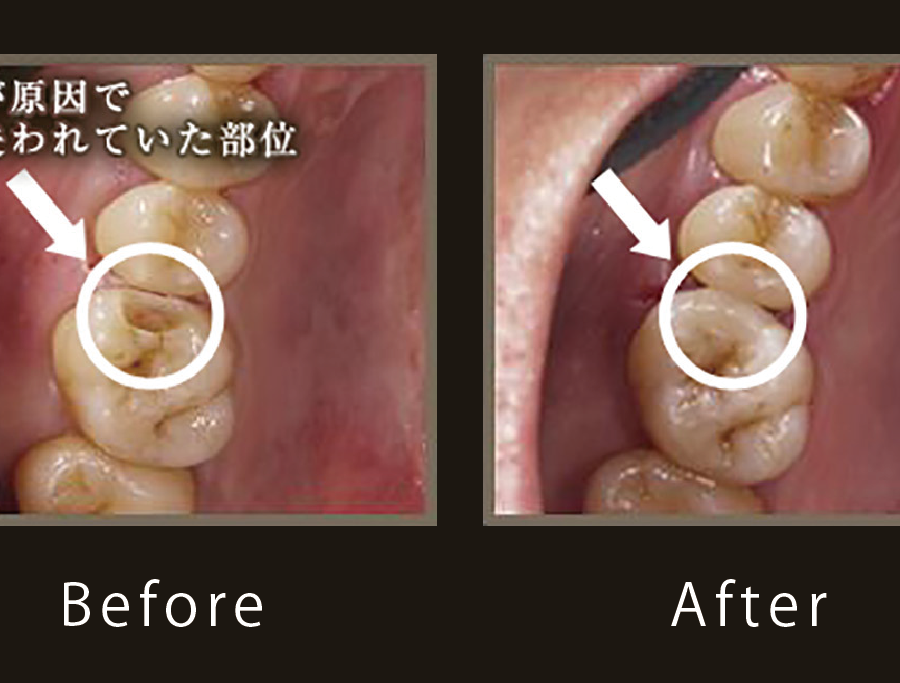

虫歯の進行した歯を救う 石神井公園 歯医者 たけのうち歯科クリニック

虫歯でお困りの方へ ヴェリ歯科クリニック